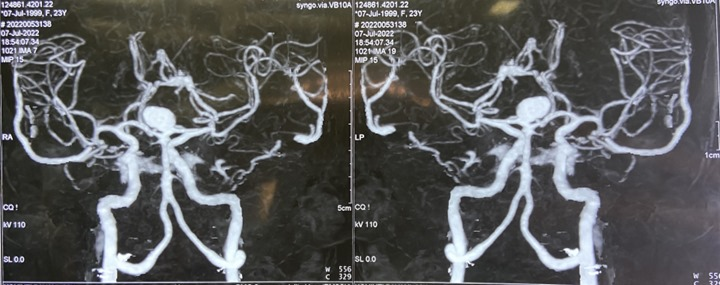

• CT brain and angiography revealed a ruptured basilar apex aneurysm. The patient underwent a left FTOZ craniotomy and clipping of the aneurysm through a half-and-half approach. The basilar top aneurysm was successfully clipped in 45 minutes.